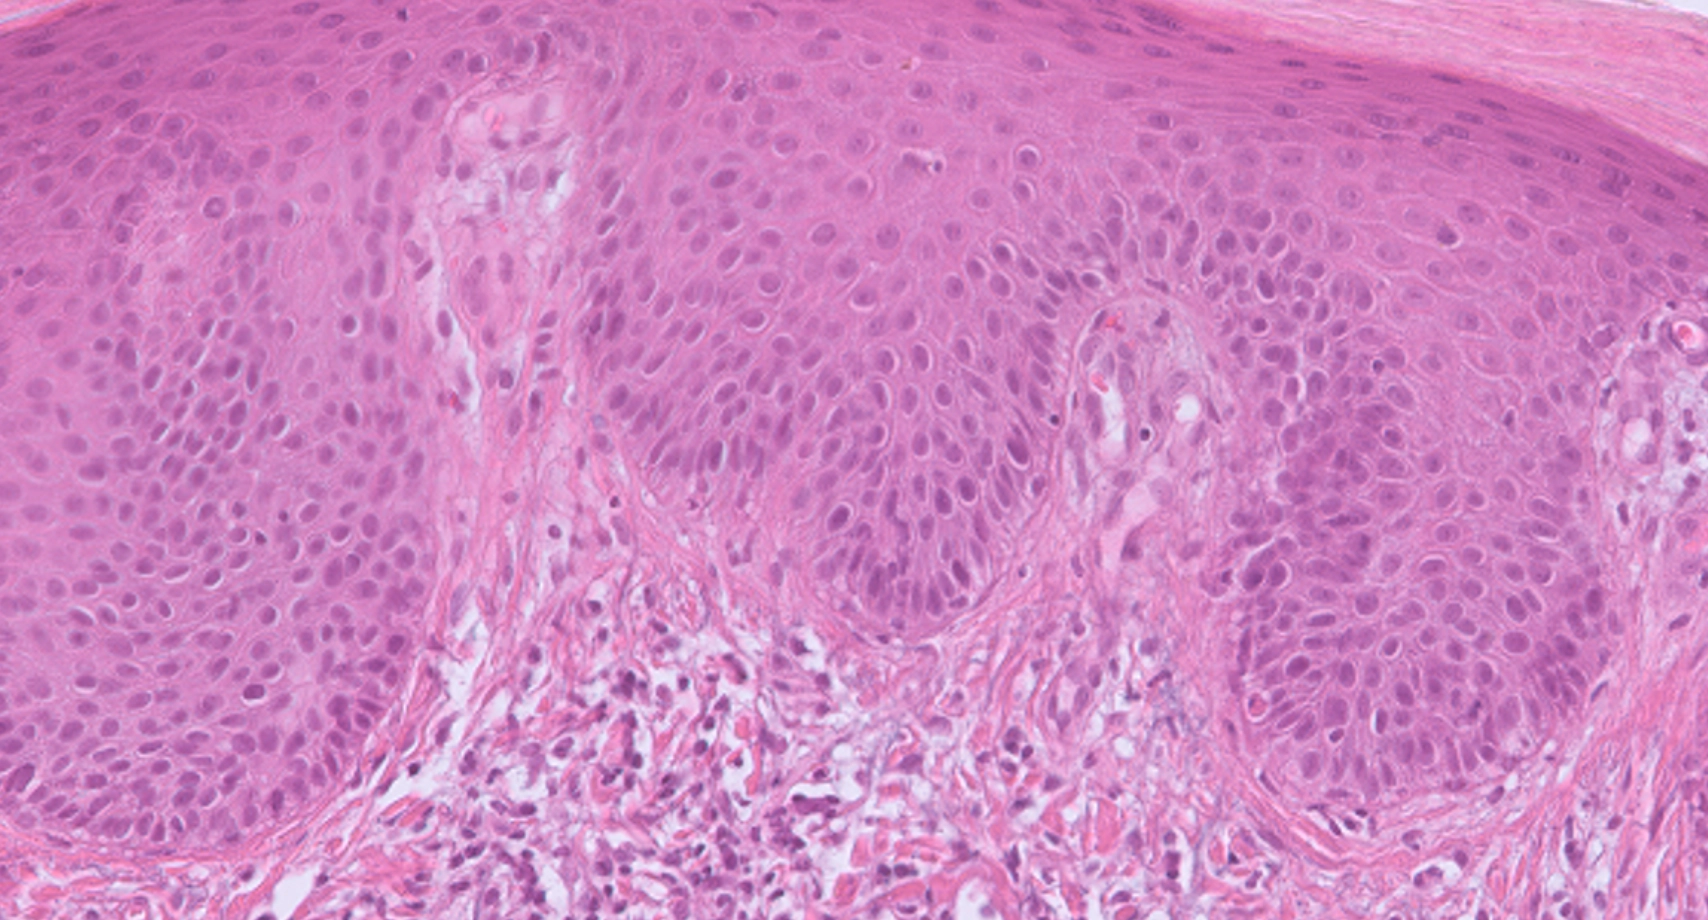

Psoriasis and eczema are among the most common inflammatory skin diseases, yet the differential diagnosis of psoriasis versus eczema remains challenging in routine dermatopathology. Overlapping clinical features and histopathological uncertainty often lead to unclear results

In a comparison involving 14 dermatopathologists, histopathological assessments showed only low to moderate agreement, especially in unclear cases. In contrast, the PsorX-LabDisk RT-qPCR assay maintained strong sensitivity and specificity, even in difficult cases, and may serve as a helpful molecular tool to improve diagnostic confidence alongside routine histopathology.